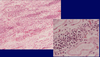

Interstitial fibrosis; seen in Chronic TID; fibrinous tissue is very pale and separates the renal tubules

Tubular atrophy; tubules shrink in diameter, the epithelium simplifies and the basement membrane thickens; seen in Chronic TID where tubules atrophy in response to slow ischemia

Chronic inflammation; uniform small lymphocytes which are remnants of a previous active inflammation. Seen in Chronic TID.

Chronic TID; fibrosis of interstitium; tubular atrophy

Chronic interstitial nephritis; with fibrosis, atrophy and chronic inflammation